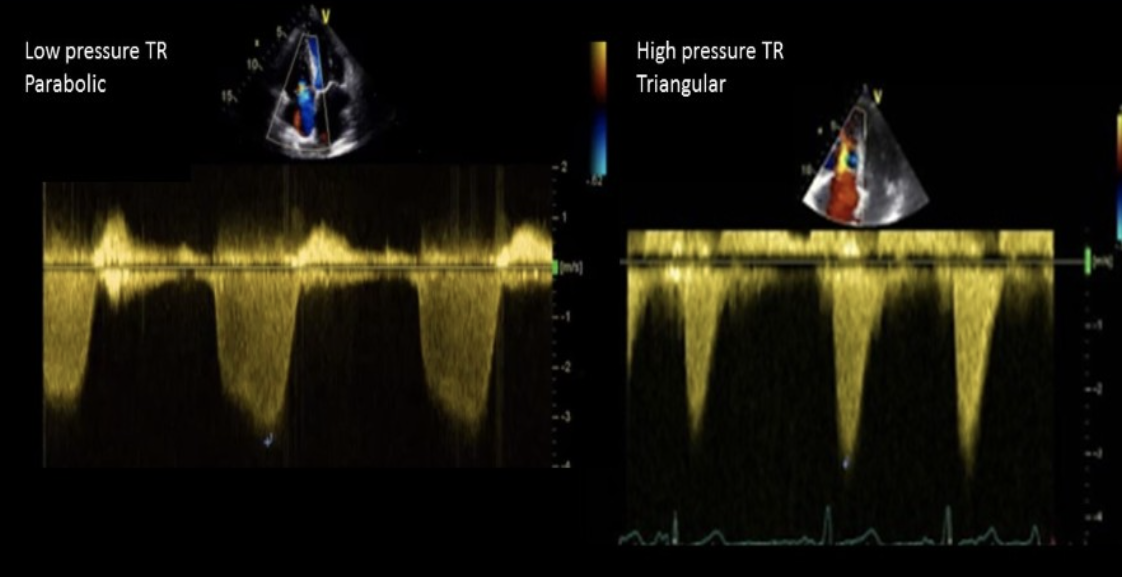

What can lead to an underestimated MVA using the pressure half time method?

Severe AI and ASD

How do you differentiate severe MS from AI on Doppler evaluation?

AI normally has a less intense Doppler signal than MS

What will decrease after a mitral commissurotomy with isolated MS?

Pressure half time